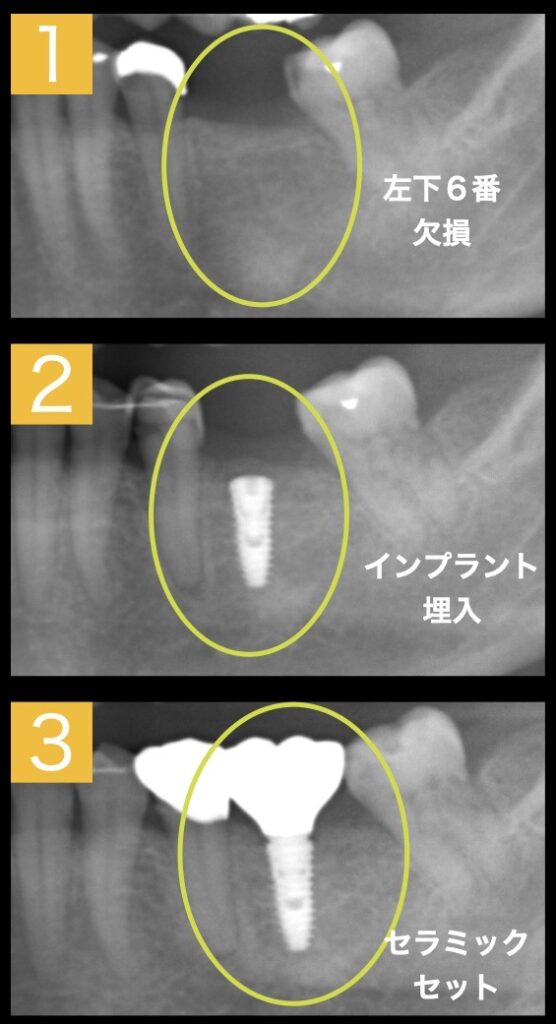

インプラント埋入までの経緯

①左下の奥歯を失ってから、1年ほど経過していたので、骨は治っていました。ただし、幅が少し足りないことがCT撮影によりわかりました。

②インプラントを埋入と同時に不足分の骨を足すマイナーGBRを行いました。

③インプラントをして4ヶ月後に歯肉の移植を行い、治癒後にセラミックをセットしました。

インプラント&セラミッククラウンセット

インプラントの上に最終的なセラミッククラウンを被せ、角化歯肉も獲得することができました。

あとは、定期的なメンテナンスに来て頂きクリーニング、噛み合わせ調整など経過観察していきます。